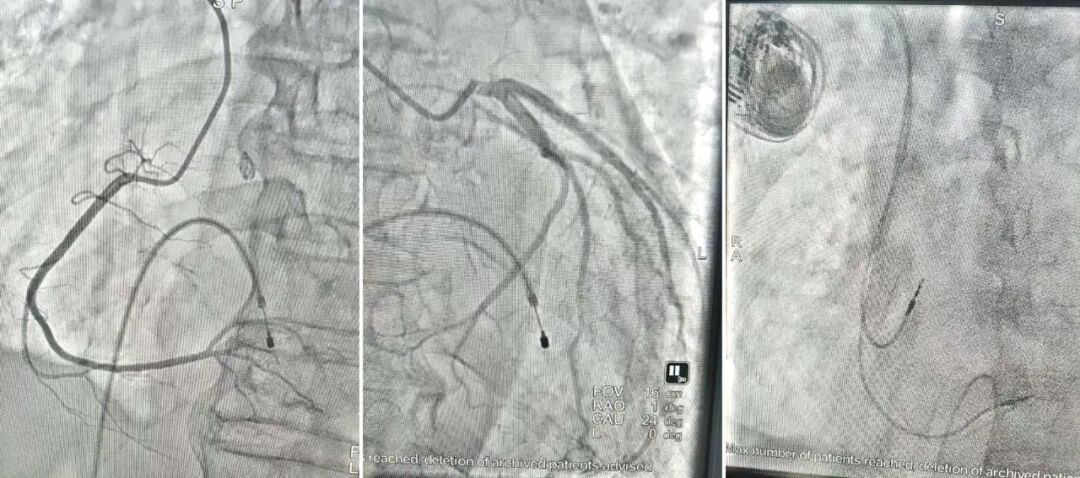

患者经医联体绿色通道转入西安市中心医院经开院区后,心血管内科团队迅速接手,为明确心脏骤停的根本原因,并确保检查过程中的绝对安全,医疗团队在临时起搏器的保护下,为患者进行了冠脉造影检查,造影结果显示其冠状动脉血管通畅,排除了急性心肌梗死的可能。最终,该院心血管内科团队精准锁定病因——“三度房室传导阻滞”,即心脏的“电路系统”完全中断,导致心跳极度缓慢乃至停搏,这正是引发此次生命危机的元凶。

在临时起搏器的保护下,患者心律趋于稳定,意识恢复。但要根本性解决问题,必须植入永久起搏器。数日后,吴冠吉主任团队为患者成功实施了“双腔永久起搏器植入术” 。手术团队技艺精湛,将心房和心室电极精准放置于理想位置,测试参数完美,起搏器工作稳定。随后,顺利撤除了临时起搏器。手术圆满成功,患者安返病房。